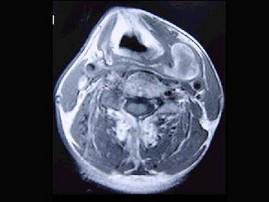

问题 男性,40岁,发现左侧颈部小包块,CT、MRI检查如图所示,请选择最可能的诊断 ( )

选项 A、肿大淋巴结 B、副神经节瘤 C、神经纤维瘤 D、海绵状血管瘤 E、神经鞘瘤

答案 D